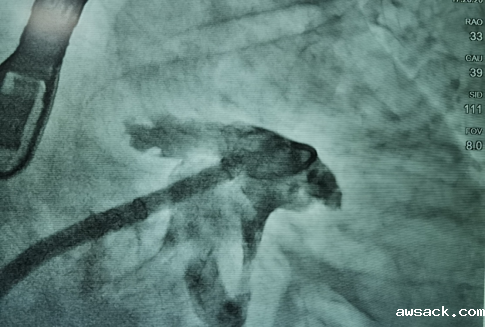

封堵前左心耳造影